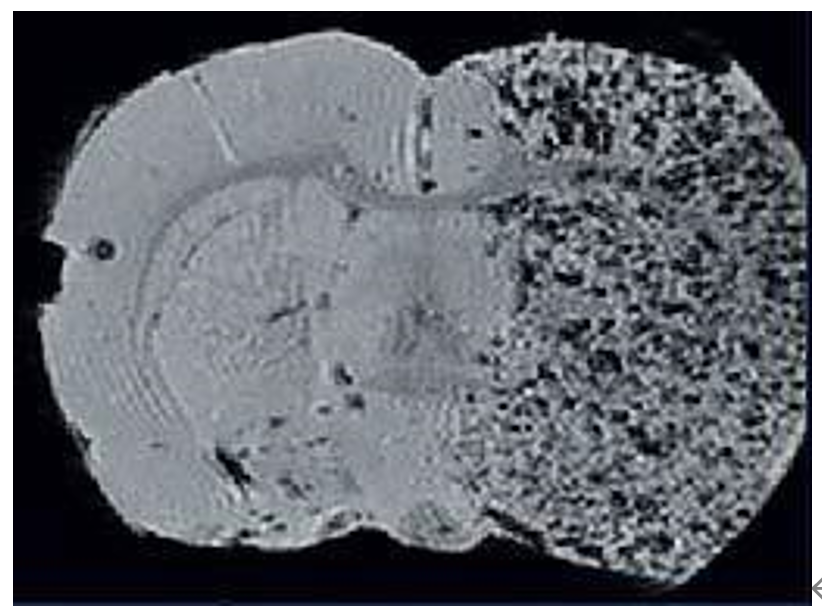

1、高分辨率神經(jīng)解剖結(jié)構(gòu)

布魯克結(jié)合超高磁場(chǎng),先進(jìn)的相陣控線圈和譜儀技術(shù)提供完美品質(zhì)的結(jié)構(gòu)形態(tài)成像。超高空間分辨率可以顯示精細(xì)的顯微組織結(jié)構(gòu)。領(lǐng)先的磁共振成像技術(shù)在超高磁場(chǎng)下提供完美的對(duì)比度。

磁共振成像低溫探頭增加150%的靈敏度,清晰顯示小鼠腦部細(xì)胞層狀結(jié)構(gòu)(小腦的顆粒層和浦肯雅細(xì)胞層),空間分辨率達(dá)到 50μm: